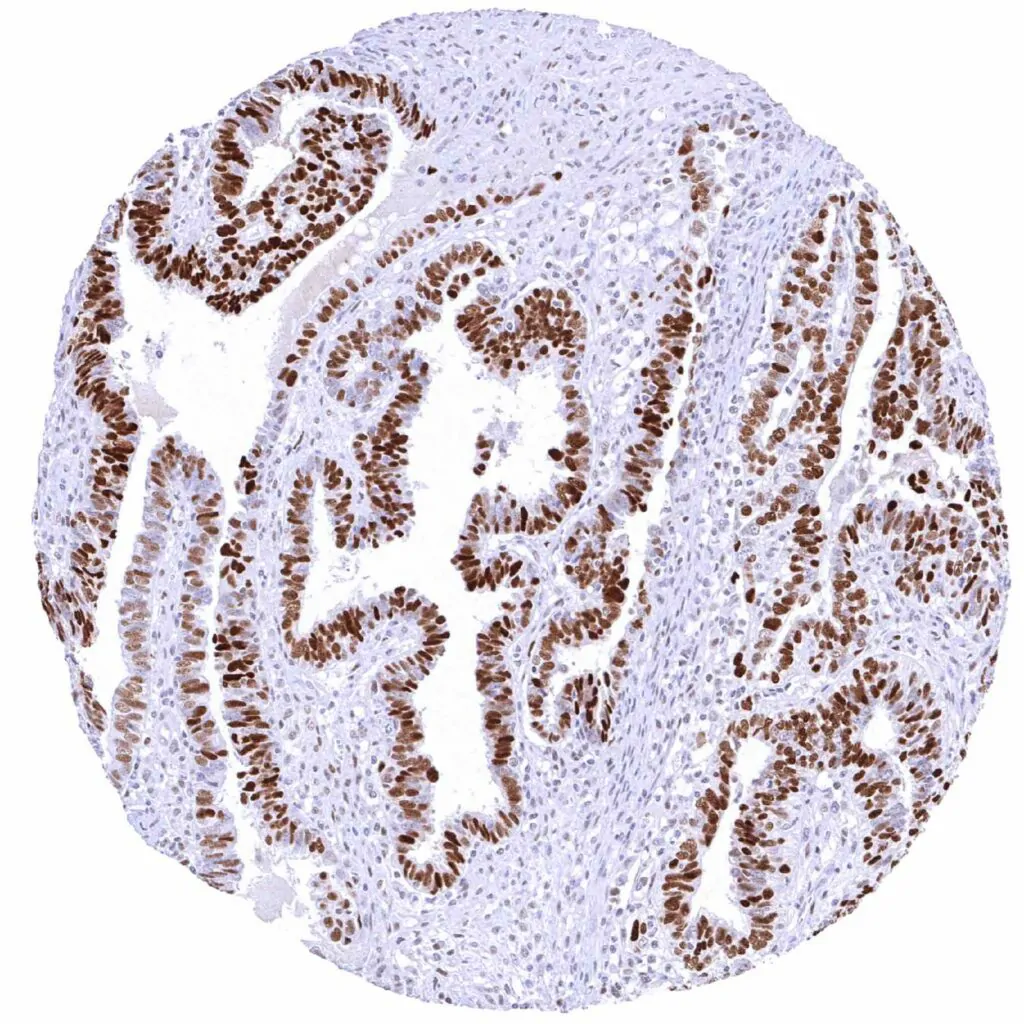

Cyclin E1 antibody [MSVA-898R] HistoMAX™

Ovary – Endometroid carcinoma with strong Cyclin E1 positivity of most tumor cells